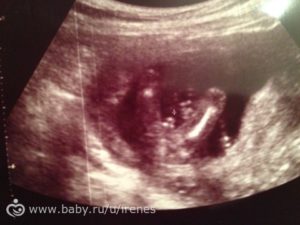

На фото Узи на 15 неделе беременности можно увидеть, как плод активно развивается и становится похожим на маленького человека, своими успехами радуя будущую маму

На УЗИ, которое проводят на 15-й неделе беременности будущей матери видно, как активно двигает малыш ручками, ножками. Этот срок характеризуется усиленным развитием мышечной системы.

На экране же малыш выглядит длиною около пальца. Если выполняют 3D УЗИ, то на экране видно недовольство крохи, которое проявляется при нажатии на живот датчиком. Ребенок может хмурить бровки, хвататься за пуповину, активнее двигаться.

И хотя существо, которое можно увидеть на экране, имеет длину около 10 см, уже можно рассмотреть его щечки и глазки с бровками.

Более того, нередко можно увидеть и недовольную реакцию ребенка на притеснения извне — надавливание датчиком УЗИ на живот заставляет малыша хмуриться и пытаться защититься руками.